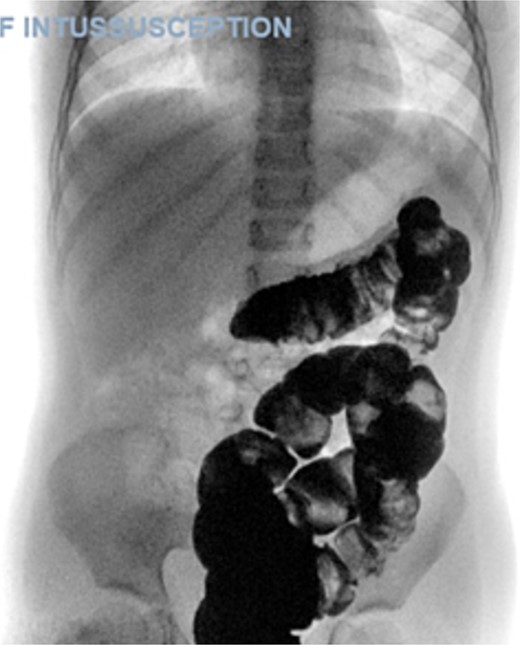

The blood tests showed raised inflammatory markers. An abdominal ultrasound confirmed the presence of intussusception (Fig. 2). A decision was made for a laparoscopic reduction of the intussusception and inspecting for a leading point. A MD was demonstrated and resected accordingly (Fig. 3). The location of intussusception was at the ileo-cecal area. The affected bowel was viable. The position of the MD was in the terminal ileum and it was the lead point for the intussusception. No lymph node involvement. Also, a tumor located at the base of the MD ~4 mm from the resection margin, was found and resected.

Meckel’s diverticulum as a lead point for recurrent intussusception.